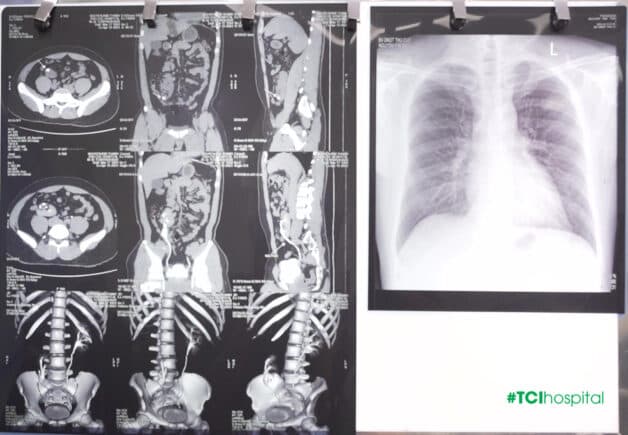

Trước đó, khi tham gia các hoạt động mạnh, chạy, nhảy, chơi đá bóng, bệnh nhân N.K.T sẽ gặp tình trạng tiểu máu không rõ nguyên nhân. Kết quả chẩn đoán hình ảnh tại Bệnh viện ĐKQT Thu Cúc cho thấy anh T. có tình trạng thận phải lạc chỗ nằm thấp phía trước cơ thắt lưng chậu phải, trục thận xoay ra ngoài, bể thận có sỏi kích thước 6x10mm.

Hình ảnh kết quả chẩn đoán thận lạc chỗ của bệnh nhân N.K.T (Ảnh: TCI)